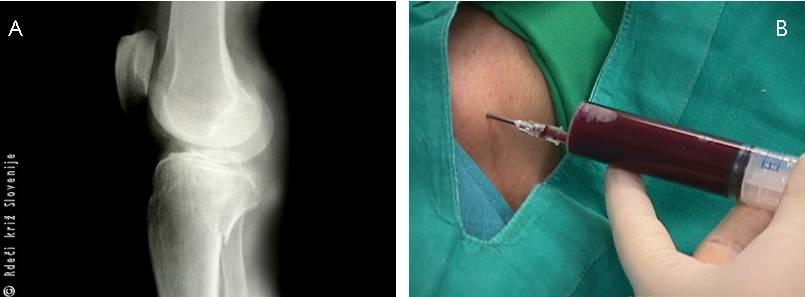

Slika 11

A – Na terenu težko ocenimo ali gre ob poškodbi sklepa tudi za zlom, zato je potrebno rentgensko slikanje, ki je v tem primeru pokazalo zlom v predelu zgornjega dela golenice.

B – Ob poškodbi znotrajsklepnih struktur praviloma pride do izliva krvi v sklep, ki jo je potrebno odstraniti s punkcijo.